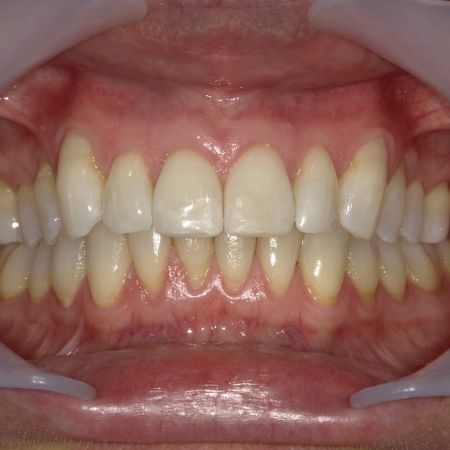

Fallbeispiel 4

Fallbeispiel 4 zeigt einen häufigen Befund bei erwachsenen Patienten: Die Stellung der Schneidezähne hat sich in beiden Zahnbögen im Laufe der Jahre erkennbar verschlechtert, und die Patienten fühlen sich dadurch zunehmend beeinträchtigt. Die in diesem Beispiel nur geringgradigen Abweichungen im Oberkiefer ließen sich mit nahezu unsichtbaren, herausnehmbaren Alignerschienen behandeln, während die Korrektur der stärkeren Schachtelstellung der unteren Frontzähne eine festsitzende Zahnspange erforderte. Auch hier ist nach der Korrektur die Verwendung innenliegender aufgeklebter Stabilisierungsdrähte über viele Jahre hinweg ratsam.

Nach der Behandlung

(Dauer der aktiven Behandlung: Im Oberkiefer 7 Monate, im Unterkiefer 1 Jahr, 4 Monate)

Sehr gute Stabilität nach 12 Jahren